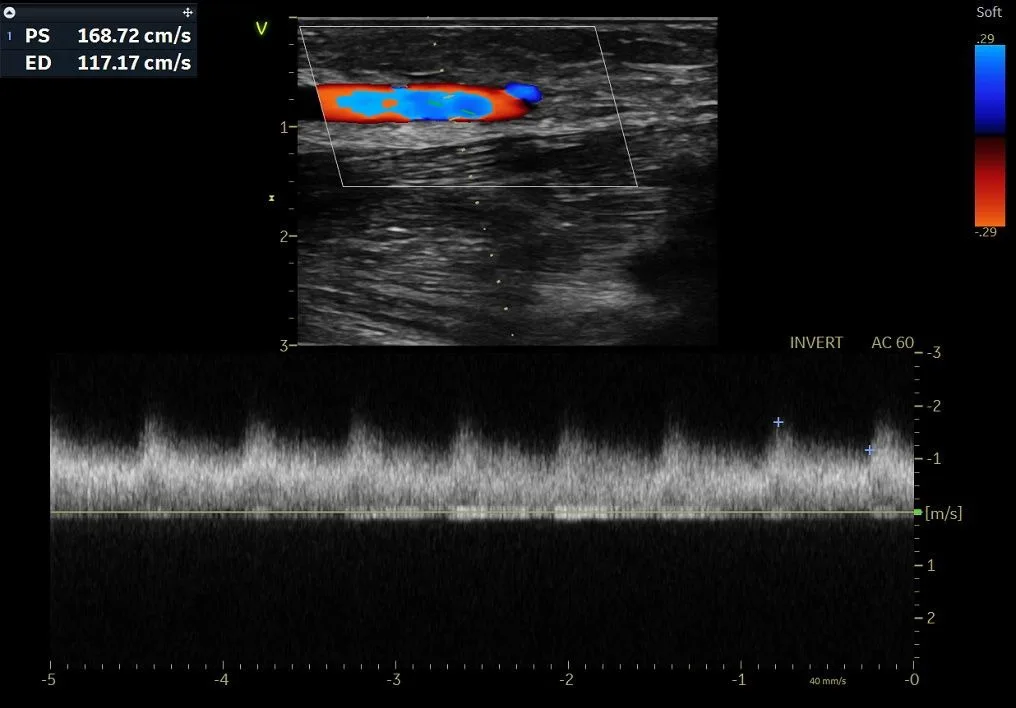

Fistula narrowing or blockage with facial swelling (central vein occlusion) and abnormal flow.

Restoring blood flow in blocked or dysfunctional AV fistulas.

Detailed evaluation with ultrasound or imaging to clearly identify the problem.